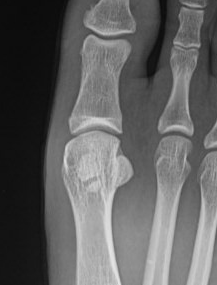

Imaging

Bilateral standing xray can help

Unclear if bipartite or stress fracture

Irregular borders suggest fracture rather than bipartite

CT demonstrates irregular borders consistent with fracture of tibial sesamoid

Edema on T2 MRI indicates likely acute fracture